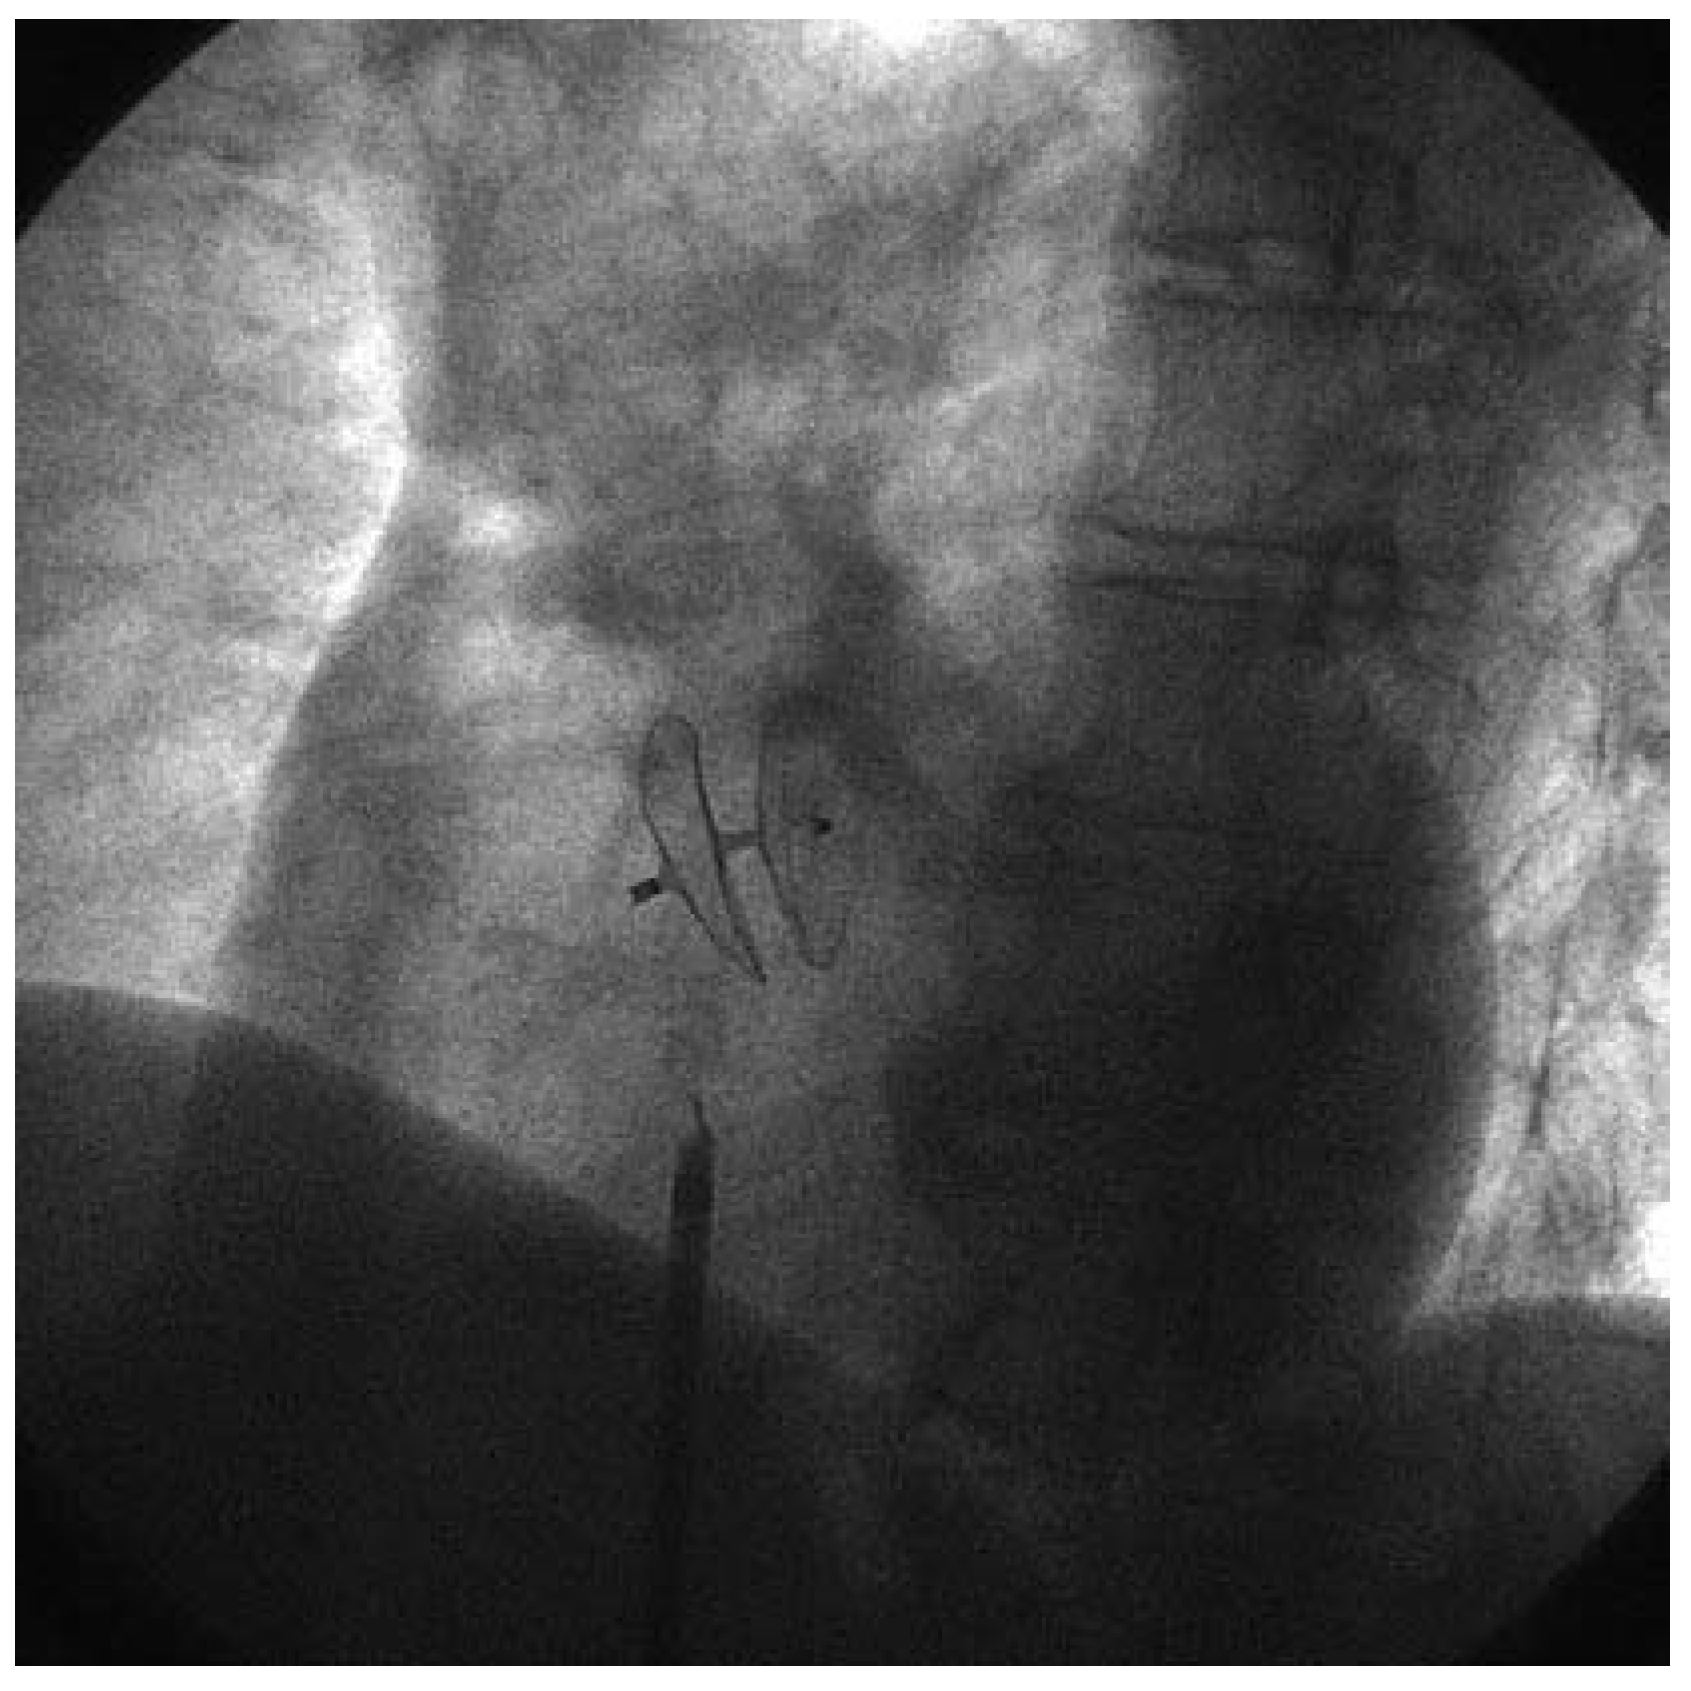

Figure 1. Deployment einer Cribier-Edwards-Aortenklappe bei einer 90jährigen Patientin durch Drs John Webb und Lukas Altwegg, St. Paul’s Hospital, Vancouver, Canada.

Bei all diesen Erfolgen und der Bedeutung der koronaren Herzkrankheit sollten andere, weniger häufige, jedoch klinisch bedeutsame Krankheitsbilder aus der kardiovaskulären Medizin nicht vergessen werden. So sind auch die Klappenleiden, vor allem im Bereich der Mitral- und Aortenklappe, für viele Patientinnen und Patienten symptomatisch und bezüglich der Prognose bedeutsam. Mit der Überalterung der westlichen Gesellschaften hat vor allem die degenerative Aortenstenose heute eine enorme Bedeutung erlangt. Sie tritt vornehmlich in der ältesten Altersgruppe auf, insbesondere bei 70- bis über 80jährigen Patientinnen und Patienten. Das Leiden beeinträchtigt die Lebensqualität der Betroffenen erheblich und führt zu Atemnot, Angina pectoris, Schwindel, zerebrovasklulären Embolien und zum plötzlichen Herztod. Durch die Einführung der Echokardiographie wurde die Diagnose und Gradierung dieses Klappenleidens auf einfache und überall verfügbare Weise möglich. Die Entwicklung mechanischer und biologischer Klappen für herzchirurgische Eingriffe hat zudem die operative Behandlung dieser Erkrankungen stark verbessert. Heute lässt sich ein Aortenklappenersatz auch bei älteren Patientinnen und Patienten über 80 Jahre mit einer geringen Mortalität und Morbidität durchführen. Dennoch ist für viele, besonders polymorbide Patientinnen und Patienten dieser Eingriff immer noch mit einem erheblichen Risiko verbunden. Entsprechend hat sich die interventionelle Forschung der letzten zehn Jahre darum bemüht, perkutane implantierbare Aortenklappen verfügbar zu machen (Figure 1). Obschon der Eingriff immer noch nur im Rahmen von Protokollen und bei Hochrisikopatienten, welche durch Herzchirurgen abgelehnt werden, in Betracht gezogen wird, hat die Technik wie auch das verfügbare Material enorme Fortschritte gemacht. Heute sind verschiedene Klappen verfügbar, welche mit immer noch grossen Schleussen femoral retrograd über die Aorta eingeführt und in der Aortenwurzel mit einem Ballon implantiert werden können. Die Resultate der ersten kleinen Serien sind ermutigend und es ist absehbar, dass der perkutane Aortenklappenersatz zumindest bei chirurgischen Hochrisikopatienten in mittelbarer Zukunft routinemässig verfügbar wird.